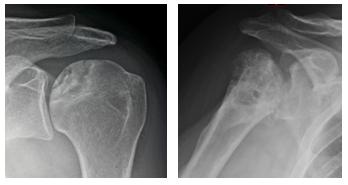

La più frequente è l’artrosi, che comporta rispetto alla spalla normale (fig. 3) la perdita delle cartilagini di rivestimento con conseguente scomparsa dello spazio articolare tra omero e scapola, la deformazione delle superfici articolari e la formazione di escrescenze ossee dette osteofiti (fig. 4): a volte avviene spontaneamente con l'invecchiamento, altre volte è favorita e condizionata da danni precedenti all’articolazione, ad esempio traumi severi o le ripetute lussazioni di spalla.

Una variante particolare di artrosi è quella che consegue a lesione massiva della cuffia dei rotatori, in cui l’omero risale verso l’alto perdendo la centrazione con la glena. Si parla di artropatia da lesione inveterata di cuffia (fig. 5).

Poi vi sono le malattie reumatiche (fig. 6) come l’artrite reumatoide, l’artrite psoriasica e altre; le necrosi della testa omerale (fig. 7), in cui una porzione della testa non riceve più apporto di sangue, degenera e si deforma (possono essere facilitate dall’uso di cortisonici e da varie altre condizioni); gli esiti di fratture mal consolidate (fig. 8) con deformazione dell’articolazione.